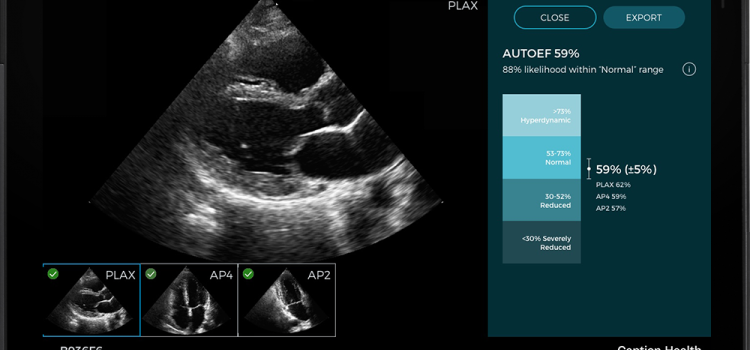

October 6, 2023 — GE HealthCare announced its Venue Family point-of-care ultrasound systems will now feature Caption ...

November 11, 2021 — Caption Health and Ultromics, developers of artificial intelligence (AI) to improve cardiac ...